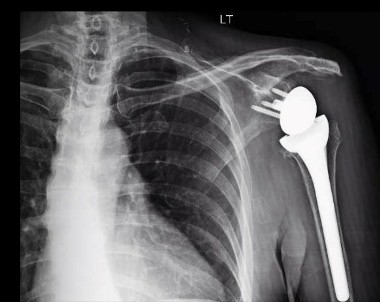

REVERSE SHOULDER REPLACEMENT

In 2004, the FDA approved a novel reverse shoulder replacement for use in the United States. Since its introduction, it has become more common than the original anatomic prosthesis. It is designed to work without a functional rotator cuff. Recovery after surgery is usually quick with predictable pain relief. Because of concerns with longevity, it is usually reserved for older patients with large irreparable rotator cuffs with arthritis. It’s considered a big surgery with potentially larger complications. Fortunately, as our experience with this procedure evolves, complications are becoming less frequent.